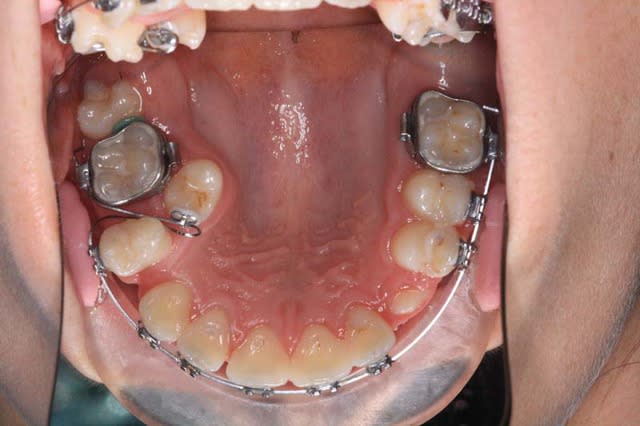

Voici, par exemple, un cas en fin de TTT.

+ Bjc.

Img 1 qmasah - Eugenol

Img 2 vtedrr - Eugenol

Img 3 zxbzaf - Eugenol

Voici un autre exemple de séparateurs sur le m cas.

(mes petits trucs)

@+ Bjc.